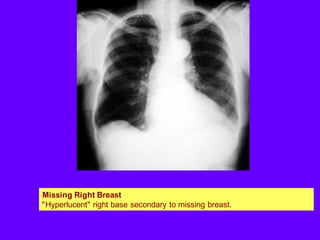

Missing Right Breast

"Hyperlucent" right base secondary to missing breast.